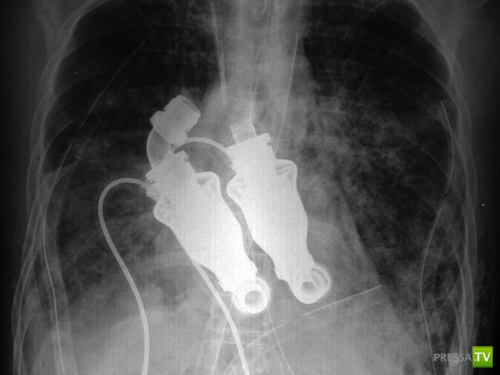

Докторам Билли Кон и Бад Фрейзер из Техасского Института Хирургии Сердца пришла идея заменить человеческое сердце специальным насосом, который позволял крови циркулировать по телу при отсутствии пульса. Они не только придумали и построили это устройство, но и успешно протестировали его на 50-ти телятах. Они познакомились с 55-летним Крэйгом Льюисом (Craig Lewis), которому осталось жить совсем немного. Когда они предложили ему и его семье поучаствовать в этом научном эксперименте и заменить сердце мужчины на новое устройство, жена безнадежно больного Крэйга дала свое согласие.

Доктора удалили сердце пациента из груди, а вместо него поставили данное революционное устройство. Операция прошла успешно. В течении дня после операции Крэйг смог уже говорить и чувствовал себя хорошо.

Таким образом, благодаря этим двум докторам-гениям Крэйг стал первым в мире человеком без сердца, также у него не было пульса!

Докторам Билли Кон и Бад Фрейзер из Техасского Института Хирургии Сердца пришла идея заменить человеческое сердце специальным насосом, который позволял крови циркулировать по телу при отсутствии пульса. Они не только придумали и построили это устройство, но и успешно протестировали его на 50-ти телятах. Они познакомились с 55-летним Крэйгом Льюисом (Craig Lewis), которому осталось жить совсем немного. Когда они предложили ему и его семье поучаствовать в этом научном эксперименте и заменить сердце мужчины на новое устройство, жена безнадежно больного Крэйга дала свое согласие.

Доктора удалили сердце пациента из груди, а вместо него поставили данное революционное устройство. Операция прошла успешно. В течении дня после операции Крэйг смог уже говорить и чувствовал себя хорошо.

Таким образом, благодаря этим двум докторам-гениям Крэйг стал первым в мире человеком без сердца, также у него не было пульса!